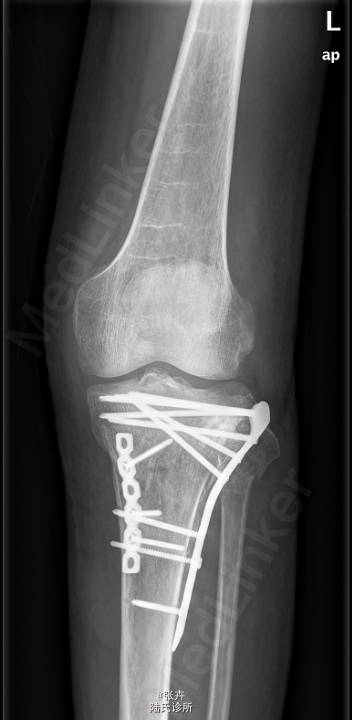

初步诊断:左胫骨平台骨折。行左胫骨平台骨折切复内固定+人工骨植骨术。

注意术后关节功能锻炼。